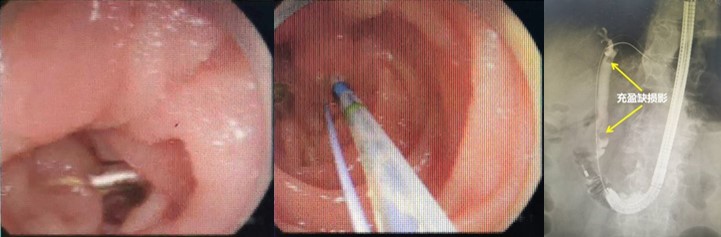

面对如此紧急的情况,干部保健病区冯建军主任联合消化内科赵刚副主任迅速启动了绿色通道,为刘爷爷进行了初步的稳定治疗,同时召集多学科专家进行紧急会诊。专家们一致决定先进行胃镜检查,了解患者既往手术方式,同时为可能的ERCP操作进行“探路”。后经胃镜检查,明确老人确实为“毕Ⅱ式远端胃部分切除”术后改变,内镜下反复寻找后,终于找到输入袢肠管以及十二指肠主乳头,同时为了后续手术时便于再次寻找,以一枚金属夹在十二指肠主乳头旁侧进行标记。

赵刚副主任凭借丰富的经验和精湛的技术,运用胃镜佩戴透明帽顺利找到前期设定的钛夹标记及十二指肠主乳头,然后利用专业器械,在内镜精细操作下,成功进行乳头括约肌切开及球囊扩张术,并最终将胆管内结石顺利取出。整个操作用时不到20分钟。